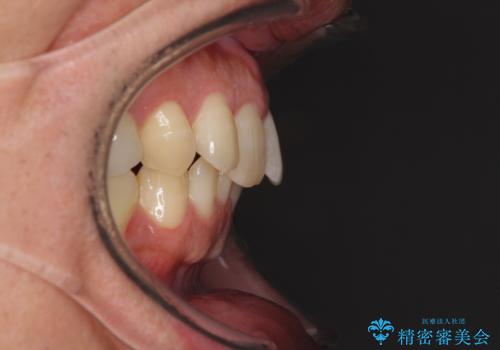

- 外に飛び出した側方の歯と、前歯のデコボコを気にして来院された患者様です。

IPR(歯と歯の間を削る)によってデコボコが解消するように設計し、インビザラインにより治療を行うこととしました。

治療途中で1年半以上通院されない時期があったため、後戻りが生じたことで治療期間が長くなってしまいました。

親知らずを抜去したことで、下顎のデコボコがきれいに解消されました。